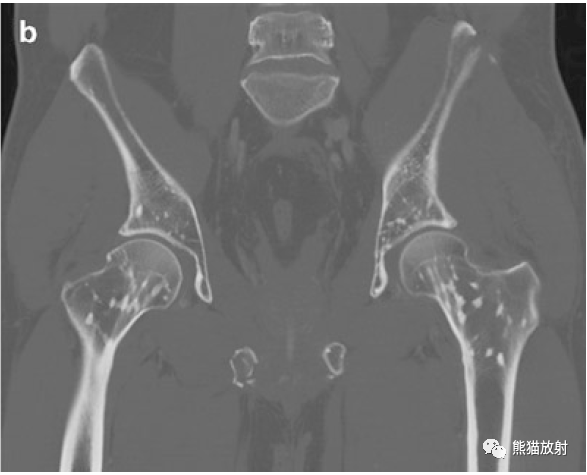

病史58岁男性,车祸后左侧骨盆疼痛。(A 58-year-old man with left sided pelvic pain following car accident.)

影像学表现股骨和骨盆骨可见多发小圆形硬化灶,X线片(a)和 CT图像(b)上都可见到左侧髂骨翼骨折。There are numerous small round sclerotic foci in the femurs and pelvic bones. Fracture of the left upper iliac wing is seen on both the radiograph (a) and CT image (b).